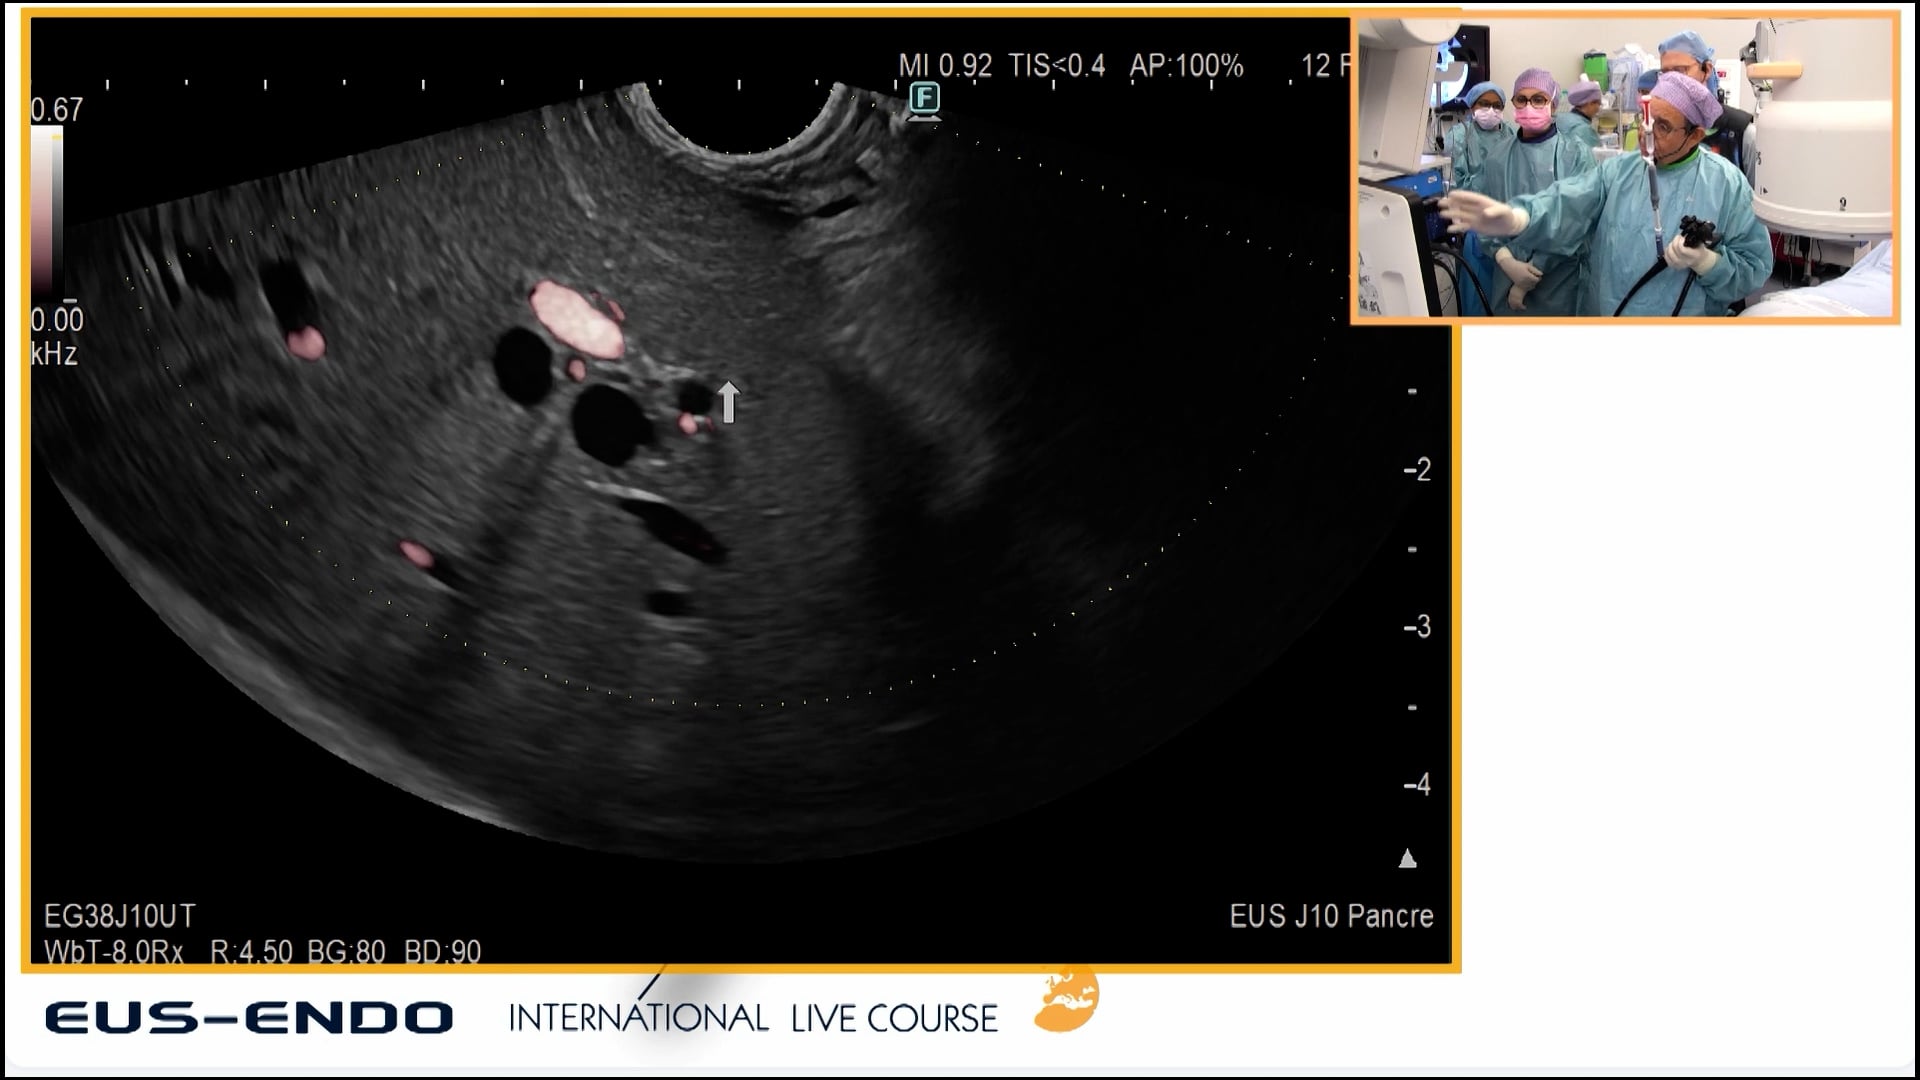

Latest on WebSurg

Résection antérieure laparoscopique avec excision totale du mésorectum avec imagerie par fluorescence et imagerie par contraste de tavelures laser (LSCI) pour évaluer la perfusion intestinale et l’application d’une matrice autologue de fibrine riche en plaquettes pour améliorer la cicatrisation anastomotique

L Baldari, A Forgione, L Boni, D Kitaguchi